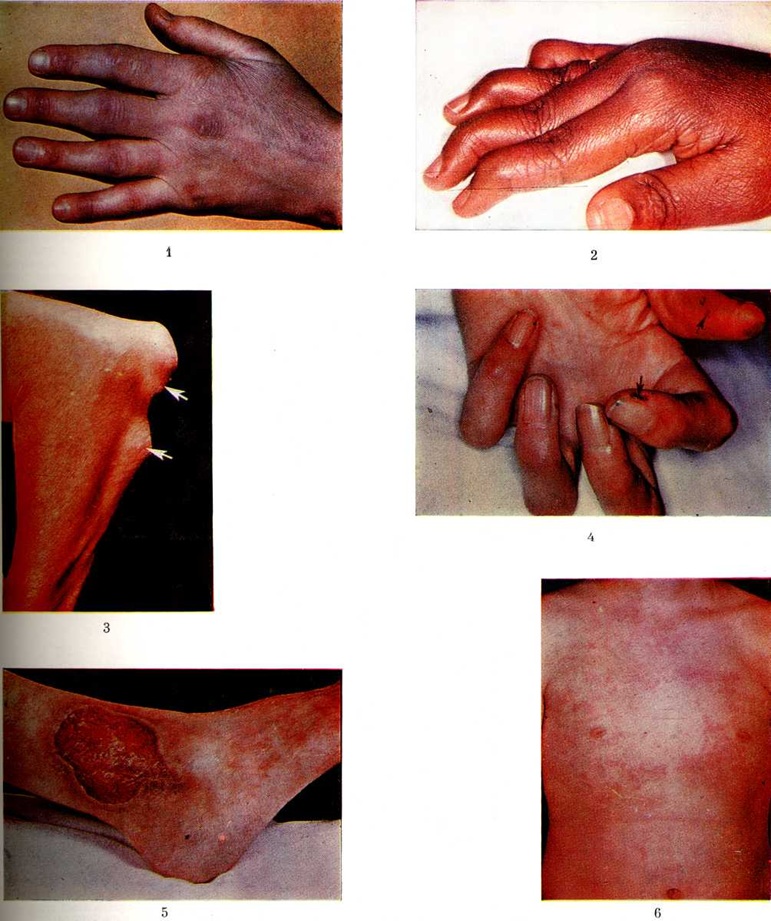

Начало болезни может быть острым и подострым, но наиболее типично постепенное медленное развитие, при котором как бы исподволь появляются стойкие боли, ощущение скованности и припухлость суставов. В ряде случаев больные отмечают связь этих явлений с различными (в основном острыми респираторными) инфекциями, травмами, нервным перенапряжением, беременностью и родами. Обычно сначала поражается небольшое число суставов, чаще проксимальные межфаланговые, пястно-фаланговые и плюснефаланговые суставы, а также лучезапястные, межзапястные и коленные. Характерно симметричное поражение суставов. При поражении проксимальных межфаланговых суставов пальцы руки приобретают веретенообразную форму (цветной рисунок 1). Примерно в 10% случаев заболевание начинается и длительно протекает в виде моно или олигоартрита крупных суставов. Боли обычно умеренные и возникают лишь при движениях. Характерное ощущение скованности в суставах более выражено по утрам.

Стойкий синовит (смотри полный свод знаний), а также воспаление суставной капсулы, сухожилий и их влагалищ и сумок, сообщающихся с суставами, приводят со временем к развитию деформаций суставов, контрактур, подвывихов, анкилозов. Некоторые виды деформаций суставов типичны почти исключительно для Ревматоидный артрит К ним относятся деформация пальцев кисти в виде «шеи лебедя» (цветной рисунок 2) — сгибательная контрактура пястно-фаланговых суставов с переразгибанием в проксимальных и сгибанием в дистальных межфаланговых суставах, деформация пальца в виде «пуговичной петли» — сгибательная контрактура проксимального и переразгибание дистального межфалангового суставов (положение пальца при застёгивании пуговицы), подвывих пястно-фаланговых суставов с отклонением пальцев в локтевую сторону (кисть в виде плавника моржа). Эти три типа деформаций составляют понятие так называемый ревматоидной кисти.

Подкожные ревматоидные узелки (обычно безболезненные, умеренно плотные, небольших размеров) чаще располагаются в области локтевого отростка и проксимальной части локтевой кости (цветной рисунок 3), а также в области суставов пальцев кистей, больших вертелов, на апоневрозе сухожильного шлема черепа и другие

Ревматоидный васкулит (поражаются главным образом сосуды мелкого и среднего калибра) лежит в основе ряда других, реже встречающихся внесуставных проявлений: точечных участков некроза, расположенных чаще всего в области ложа ногтя,— так называемый дигитальный артериит (цветной рисунок 4), безболезненных язв, располагающихся обычно на нижней трети голени (цветной рисунок 5), эписклерита, микроинфарктов или кровоизлияний в бассейне лёгочных, мозговых, коронарных или брыжеечных сосудов.

Клинические, признаки поражения внутренних органов отмечаются относительно редко. Помимо перикардита, могут наблюдаться изменения, обусловленные миокардитом (преимущественно очаговым) и эндокардитом. Известны случаи формирования пороков сердца, почти исключительно в виде изолированной недостаточности митрального (левого предсердно-желудочкового) клапана или клапанов аорты; выраженность пороков сердца обычно небольшая, нарушения гемодинамики возникают редко. Поражение лёгких при Ревматоидный артрит включает диффузный фиброзирующий альвеолит, узелковое поражение лёгочной ткани (рисунок 6), васкулит. В ряде случаев отмечается полисерозит (смотри полный свод знаний), который чаще проявляется плевритом (смотри полный свод знаний), перикардитом (смотри полный свод знаний).

У 10—20% больных наблюдается высокая температура (38—39°) с ознобами. Лихорадка имеет интермиттирующий характер, подъёмы температуры отмечаются 1—2 раза в сутки, чаще во второй половине дня; она не снижается при лечении антибиотиками и поддаётся лишь большим дозам ацетилсалициловой кислоты и особенно глюкокортикостероидам. Как правило, высокой температуре сопутствует ревматоидная (розоватого цвета) сыпь, имеющая кореподобный макулёзный характер, локализующаяся преимущественно на туловище и проксимальных отделах конечностей (цветной рисунок 6). Эта сыпь специфична для ювенильного Ревматоидный артрит и её обнаружение имеет большое диагностическое значение. Ревматоидная сыпь быстро проходит, «расцветает» во время подъёма температуры и при потирании подозрительных участков кожи (смотри полный свод знаний: Кебнера феномен).